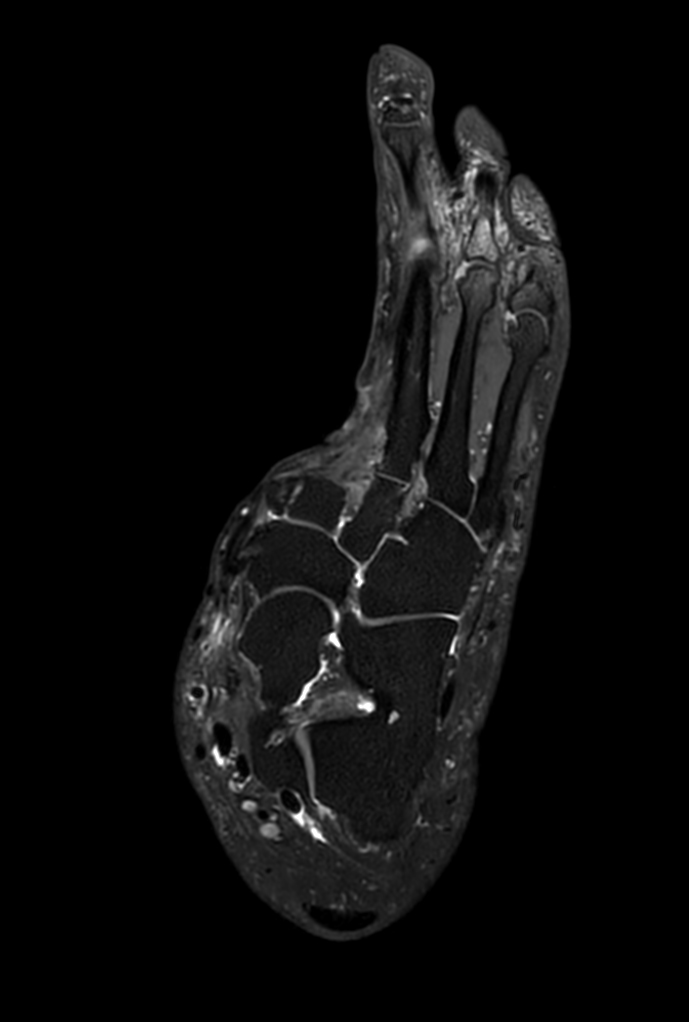

Ankle/Foot imaging post-amputation

Patient with partial amputation of the foot

3D VIEW PDw SPAIR - Axial reformat